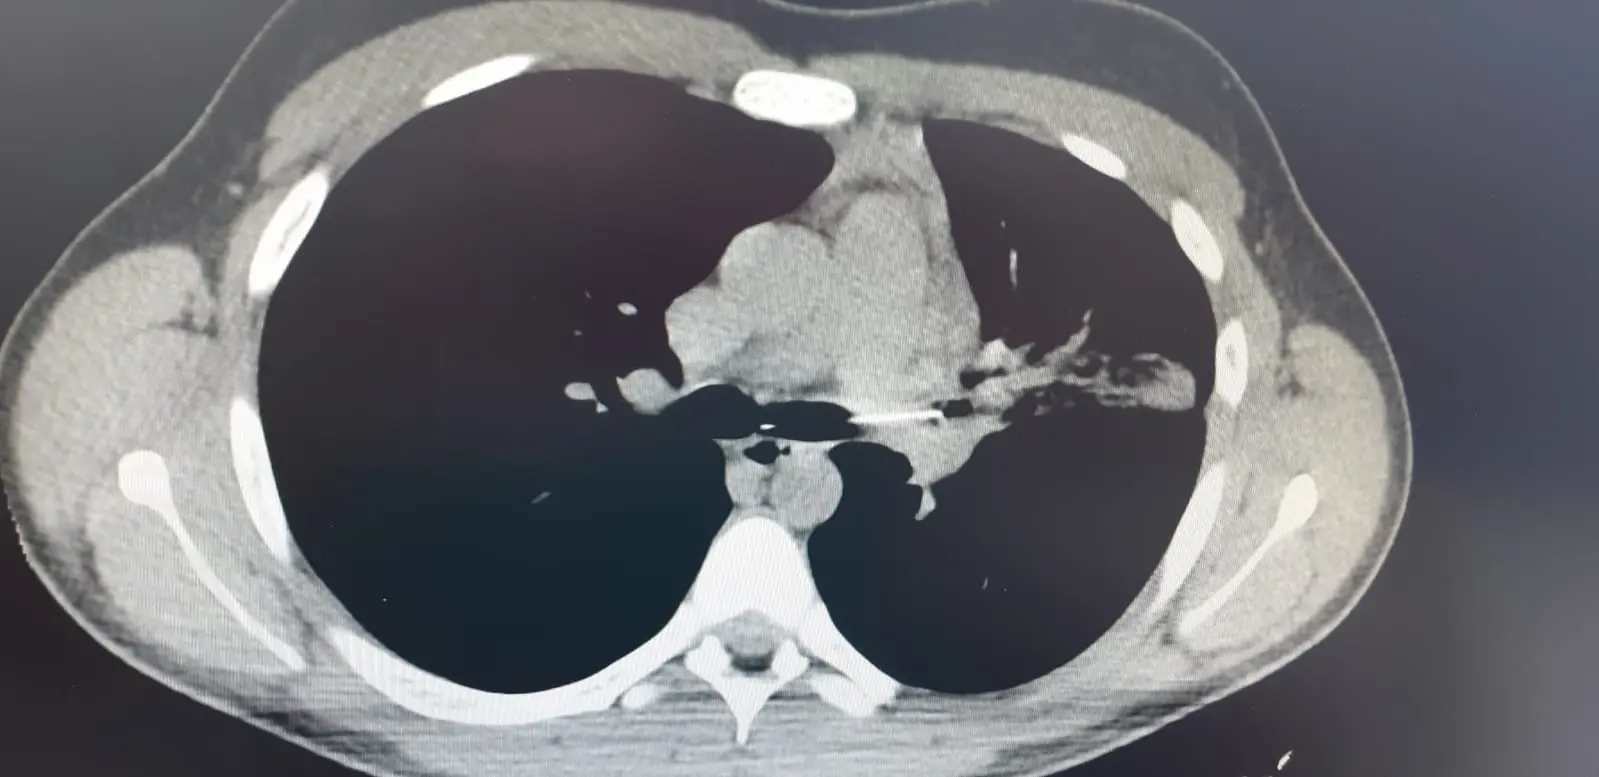

Nei giorni scorsi, l’equipe della U.O.C. di Chirurgia Toracica, diretta dal dr. Baldassare Mondello, ha eseguito una broncoscopia in anestesia generale in soccorso di un bambino che aveva accidentalmente inalato un ago.

La broncoscopia, effettuata con l’assistenza degli anestesisti dr.ssa Marilena Napolitano e dr. Pasquale Palumbo, e dei tecnici di Anestesia, dr.ssa Angela Solano e dr. Vincenzo Trunfio, ha evidenziato l’estremo distale adeso alla parete del bronco principale di sinistra e la testa dell’ago conficcata nel bronco lobare inferiore.

L’estrazione, che presentava un notevole grado di difficoltà per la sede e, soprattutto, per le caratteristiche del corpo estraneo, è stata effettuata dal Direttore di Chirurgia Toracica in sinergia con gli anestesisti e l’equipe infermieristica (strumentista: Francesca Ragona; infermiere di sala: Fabrizio Longo).

Il corpo estraneo è stato rimosso in urgenza, prevenendo temibili complicanze quali la perforazione di un’arteria o vena polmonare.